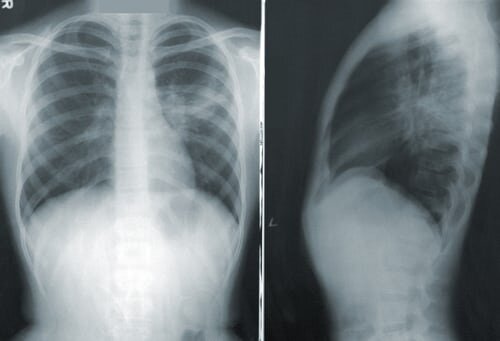

Из-за схожести симптомов коронавирус можно спутать с раком легких. У пациентов с COVID и онкобольных всегда появляется кашель, отдышка и усталость. Кроме того, даже компьютерная томография не всегда может отличить рак от коронавируса.

"На пике самой болезни, когда она переходит в пневмонию, и на фоне ярко выраженного отека ткани очень сложно поставить правильный диагноз посредством лучевых методов или общения с пациентом. Самая распространенная ошибка заключается в том, что врачи делают рентген или КТ один раз, пропуская контрольное исследование. То есть после того как пациент перенес заболевание, обязательно нужно делать контрольный снимок, и тогда будет понятно, действительно, это был ковид или все-таки пневмония ассоциирована с раком легкого.

Исход всех ковид-пневмоний - это образование фиброзных очагов в легких, и тут идет дифференциальная диагностика, которая помогает понять, действительно ли это фиброз или ранняя форма рака легкого. Кроме того, после того как пациент переболел коронавирусом, у него довольно быстро улучшается состояние, в течение одной-двух недель. А у людей с онкологией, наоборот, картина негативная и она с каждым днем ухудшается".

Что касается КТ, то если человек делает снимок не во время болезни, то рак можно увидеть в относительно ранней стадии, когда опухоль еще размером с сантиметр.